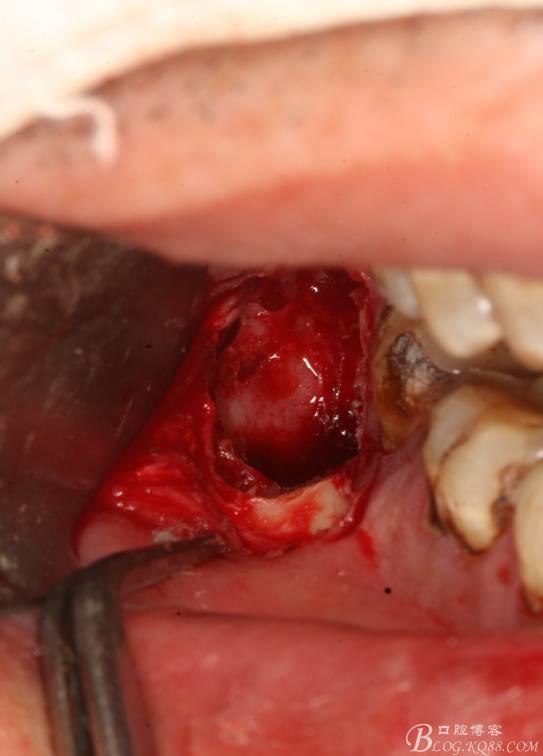

6.橫斷牙冠

7.取出牙冠

8.清理拔牙創(chuàng)